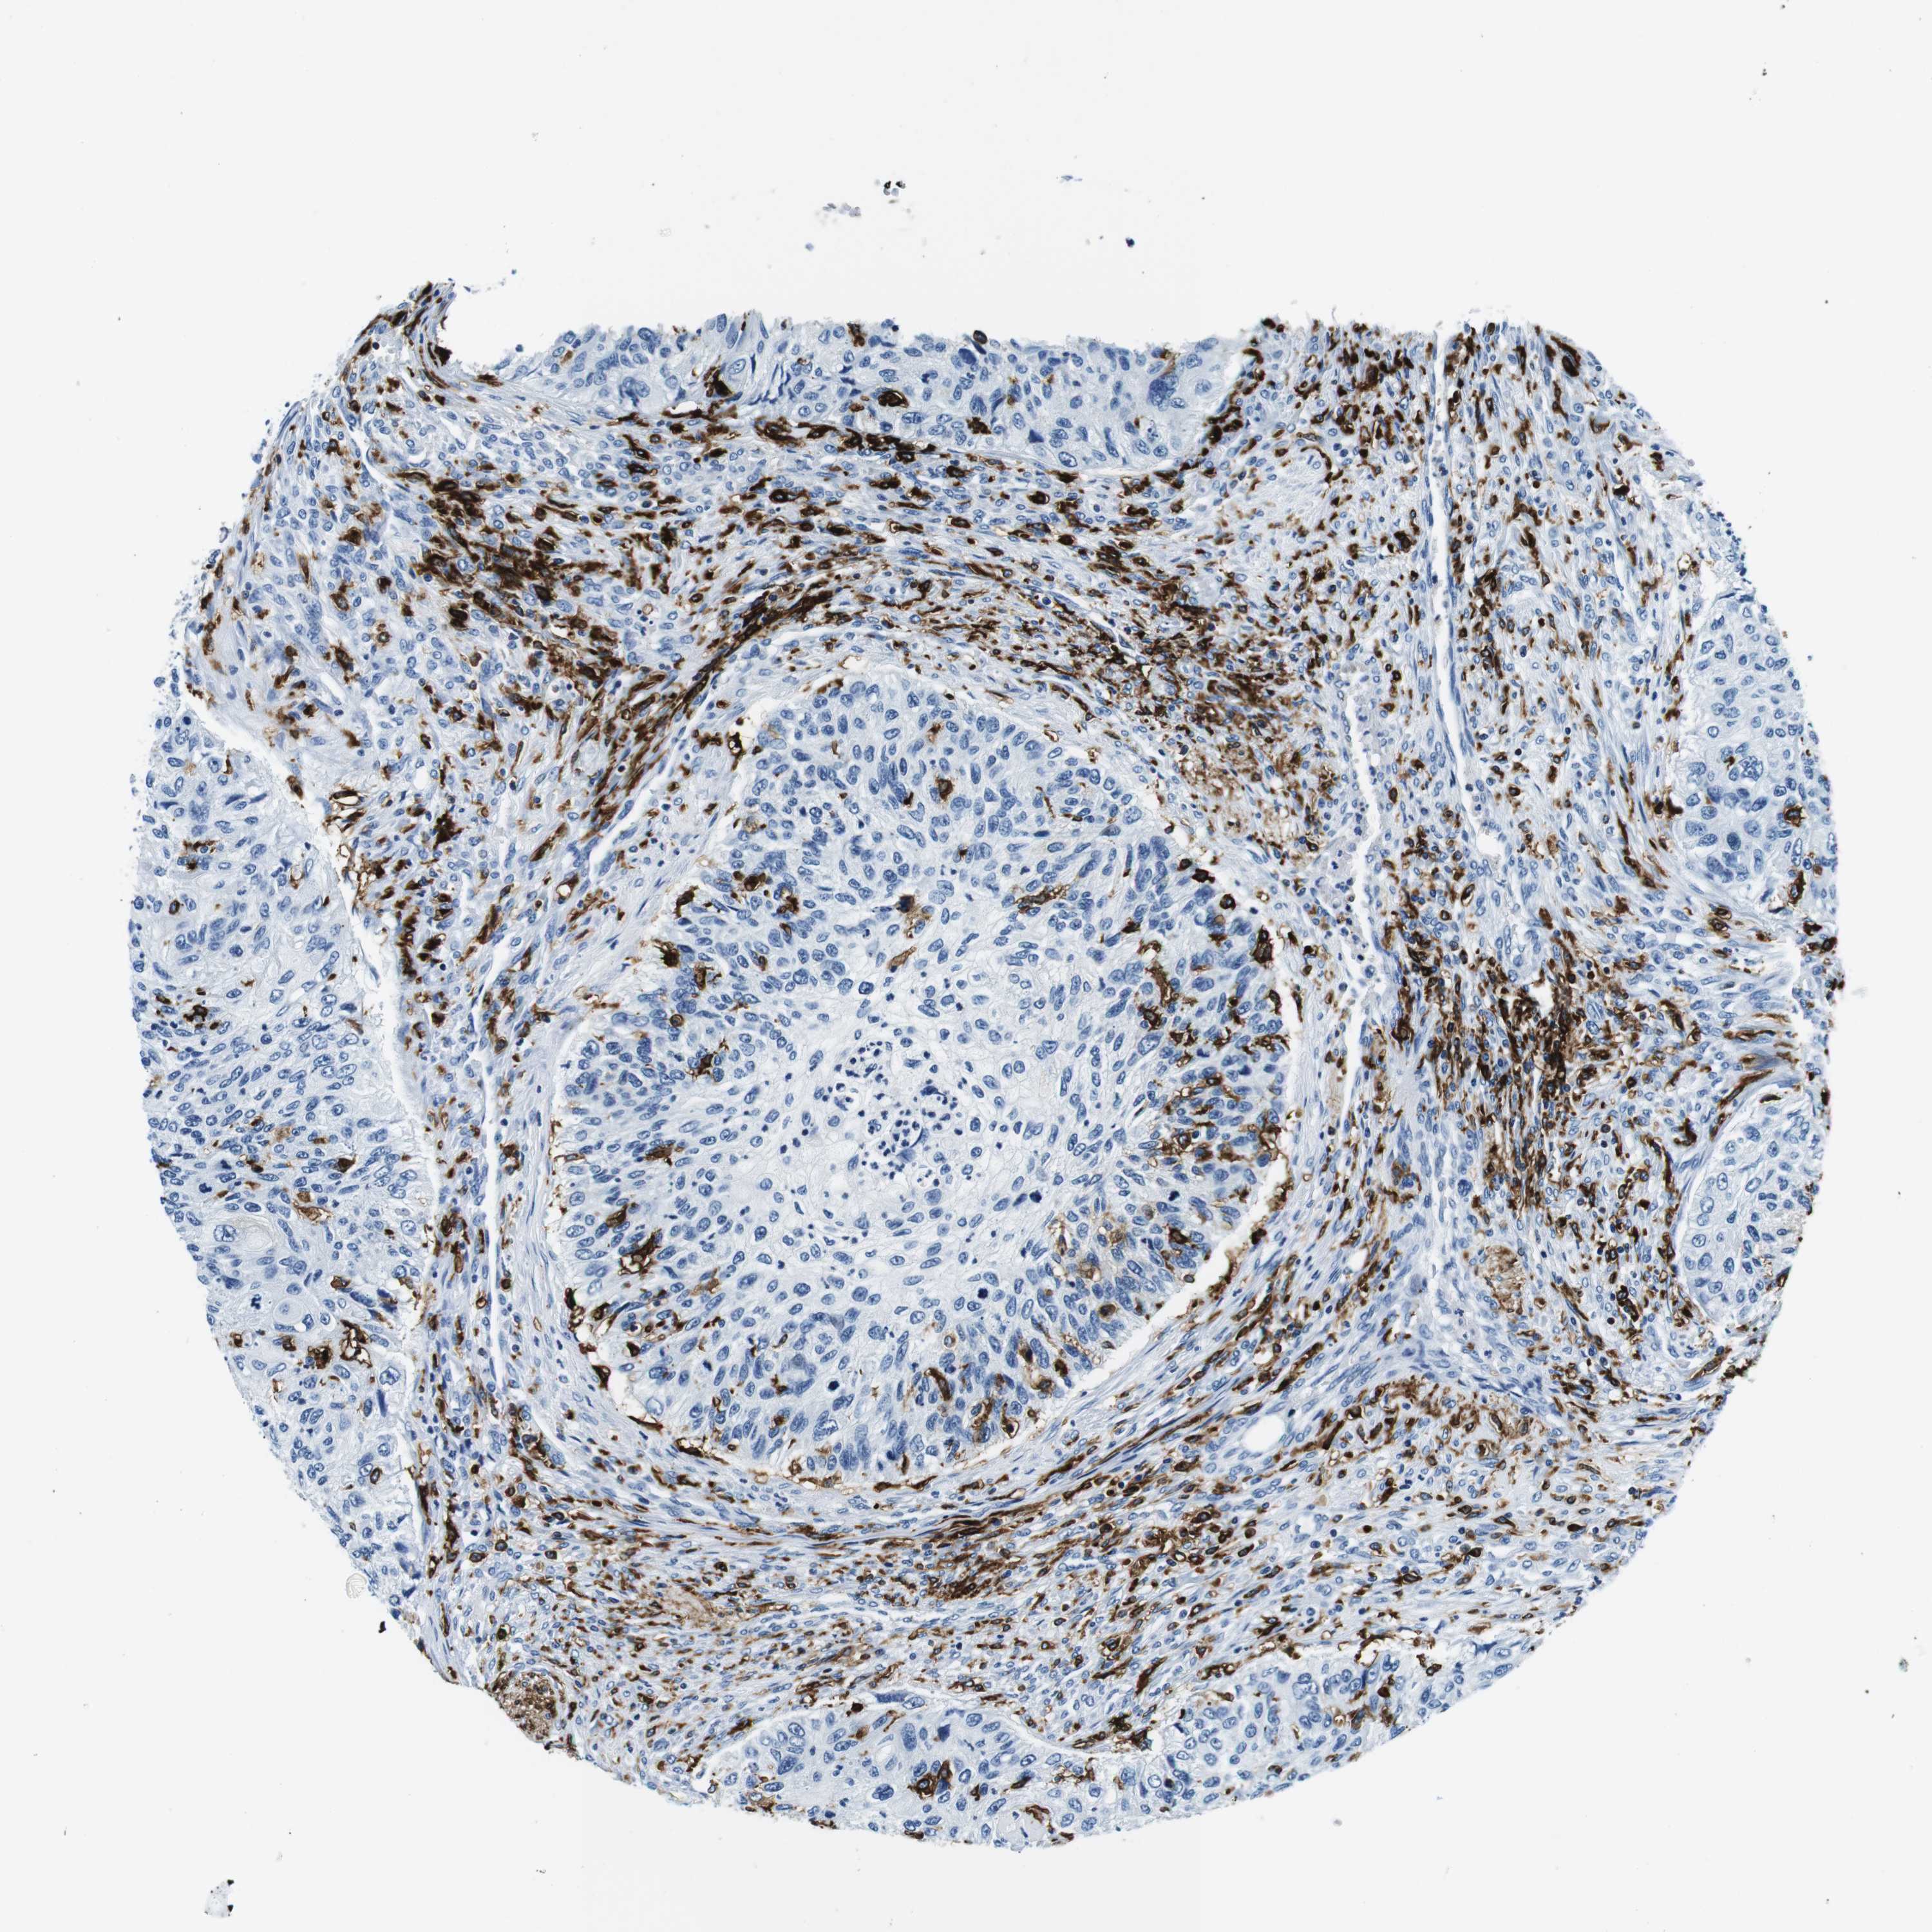

UROTHELIAL CANCER - Protein expressioni

A mouse-over function shows sample information and annotation data. Click on an image to view it in a full screen mode. Samples can be filtered based on level of antibody staining by selecting one or several of the following categories: high, medium, low and not detected. The assay and annotation is described here.

Note that samples used for immunohistochemistry by the Human Protein Atlas do not correspond to samples in the TCGA dataset.

Antibody stainingi

Antibody staining in the annotated cell types in the current human tissue is reported as not detected, low, medium, or high, based on conventional immunohistochemistry profiling in selected tissues. This score is based on the combination of the staining intensity and fraction of stained cells.

Each image is clickable and will lead to virtual microscopy that enables deeper exploration of all samples and also displays staining intensity scores, fraction scores and subcellular localization as well as patient and tissue information for each sample.

Antibody HPA043151

Antibody CAB015400

Antibody CAB034021

Staining

High

Medium

Low

Not detected

Intensity

Strong

Moderate

Weak

Negative

Quantity

>75%

75%-25%

<25%

None

Location

Nuclear

Cytoplasmic/membranous

Cytoplasmic/membranous,nuclear

Urothelial carcinoma, High grade

Urothelial carcinoma, Low grade